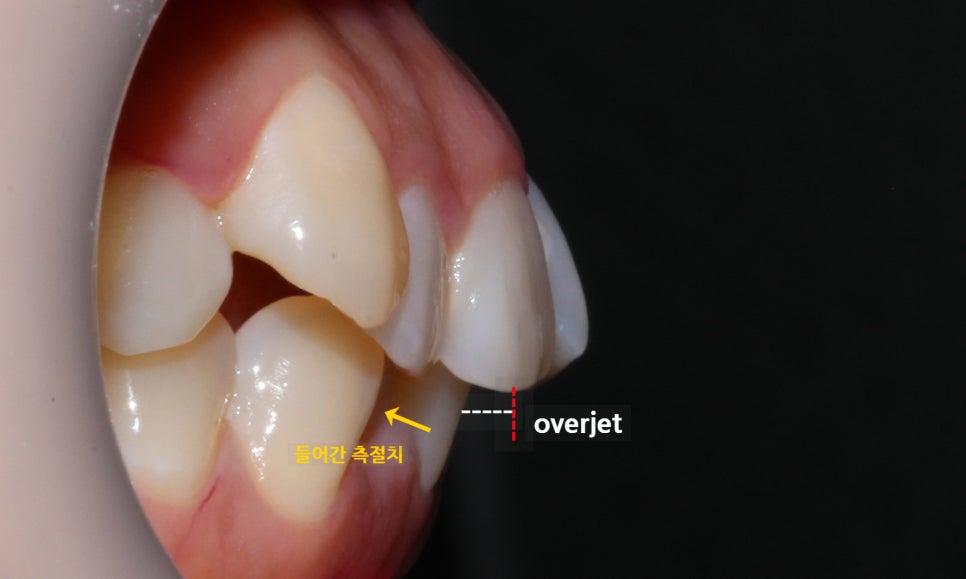

역삼역치과 덧니교정 case의 전치부

overjet 사진을 보면 하악 측절치가

주변 치아들보다 설측으로 강하게

들어가 있는 모습을 볼 수 있습니다.

이러한 경우 들어가 있는 치아를 정상적인

위치로 꺼내기 위해 교정 초기에 open coil spring을

사용하여 전치부의 공간을 마련하는 과정이 필요할 수 있습니다.